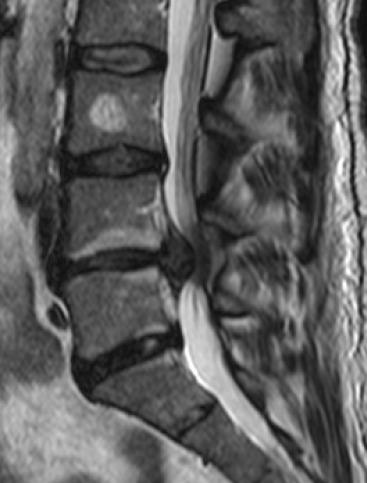

Imaging in cauda equina syndrome--a pictorial review.

Ulster Med J. 2013 May;82(2):100-8.